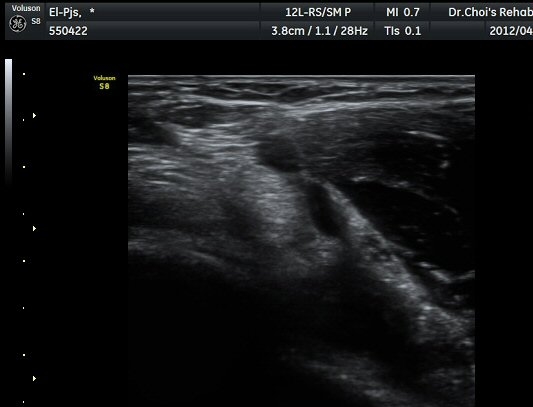

ÆÈ²ÞÄ¡ ¾ÕÂÊ È²µò¸é°Ë»ç¿¡¼­ Á¤»óÀûÀ¸·Î À̵ιڱ٠ÈûÁÙ°ú »ó¿Ïµ¿¸ÆÀÌ °üÂûµÈ´Ù(±×¸² 1).

ŽÃËÀÚ¸¦ ÆÈ²ÞÄ¡ ¸»´ÜÀ¸·Î À̵¿ÇÏ´Ï À̵ιڱ٠ÈûÁÙÀÇ ºñÈÄ¿Í ÈûÁÙ ÁÖÀ§¿¡ Àú¿¡ÄÚ ¼ö¾×Àú·ù°¡ ]

°üÂûµÈ´Ù(±×¸² 2, 3, 4, 5). ŽÃËÀÚ¸¦ ¸»´ÜÀ¸·Î À̵¿ÇÒ ¶§ ŽÃËÀÚ¸¦ ¸Ó¸®ÂÊÀ¸·Î °æ»ç(tilting)½ÃÄѾß

À̵ιڱ٠ÈûÁÙ¿¡ Á÷°¢ ÀÇ ÃÊÀ½ÆÄ Á¶»ç°¡ °¡´ÉÇÏ¿© À̵ιڱ٠ÈûÁÙÀÌ °í¿¡ÄÚ·Î °üÂûµÈ´Ù.

À̵ιڱ٠ÈûÁÙ Á¾´Ü¸é°Ë»ç¿¡¼­ ÈûÁÙÀÇ ºñÈİ¡ °üÂûµÇ³ª ÈûÁÙÀÇ ¿ä°ñµ¹±â(radial tuberosity)

ºÎÂøºÎ´Â ºñµî¹æ¼ºÀΰøÀ½¿µ(anisotopic artifact) ¶§¹®¿¡ ¶Ñ·ÈÈ÷ °üÂûµÇÁö ¾Ê´Â´Ù(±×¸² 6).